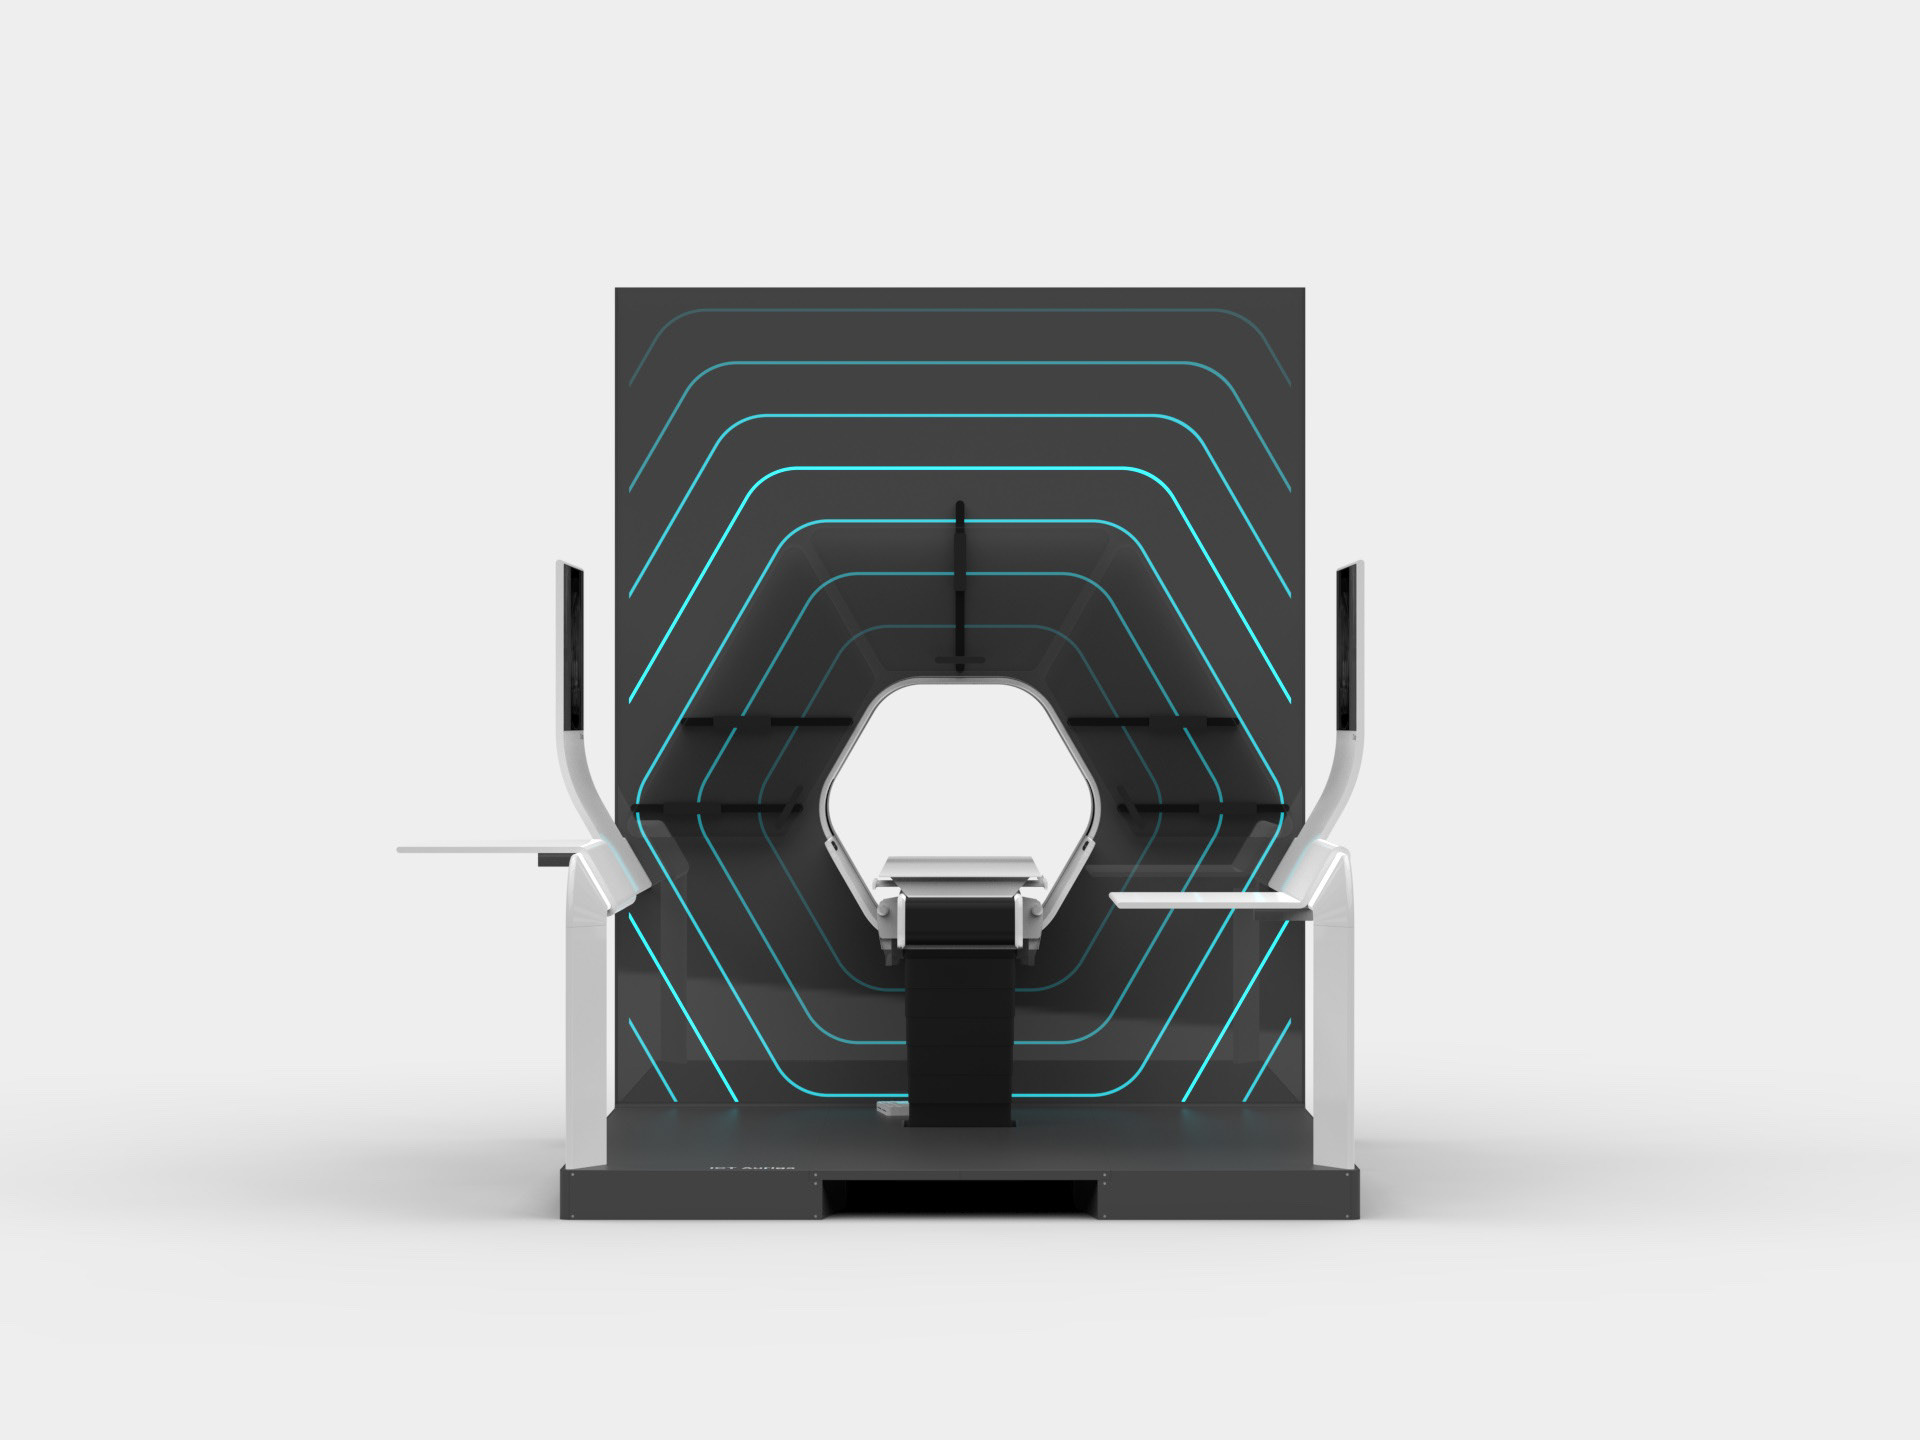

Auriga is an architecturally inspired CT device. The gantry extends to the ceiling and becomes a spatial installation. This takes away its massive “machine-character” and makes it part of the room. The gantry height is individually adapted to the given space - individuality becomes part of the product. In order to enable right- and left-handed working, the overall construction is symmetrical and intervention from both sides is equally possible.

The central design feature is the hexagonal gantry opening. It provides space for the lamps and displays. The large fronts of the gantry offer space for a display of different coloured patterns and animations, which visualize the radiation. These can be individually selected and adapted together with the overall height of the gantry. The patterns pick up on the hexagonal shape of the gantry opening and set it off. To protect the interventionists from radiation, lead glass panels and a radiation protection tray are installed. The sliding lead glass panels allow individual adaptation to the patient and the interventionists working space. The tray serves to protect the abdomen and offers a lot of foot space as well as a front leaning aid for a safe stand.

DESIGN